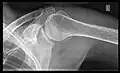

Imaging

Imaging of the shoulder includes ultrasound, X-ray and MRI, and is guided by the suspected diagnosis and presenting symptoms.

Conventional x-rays and ultrasonography are the primary tools used to confirm a diagnosis of injuries sustained to the rotator cuff. For extended clinical questions, imaging through Magnetic Resonance with or without intraarticular contrast agent is indicated.

Hodler et al. recommend starting scanning with conventional x-rays taken from at least two planes, since this method gives a wide first impression and even has the chance of exposing any frequent shoulder pathologies, i.e., decompensated rotator cuff tears, tendinitis calcarea, dislocations, fractures, usures, and/or osteophytes. Furthermore, x-rays are required for the planning of an optimal CT or MR image.[23]

X-ray

Projectional radiography views of the shoulder include:

AP-projection 40° posterior oblique after Grashey

The body has to be rotated about 30 to 45 degrees towards the shoulder to be imaged, and the standing or sitting patient lets the arm hang. This method reveals the joint gap and the vertical alignment towards the socket.[24]